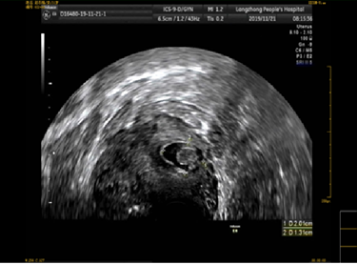

该患者孕囊位于子宫切口处肌壁内,且该处肌层菲薄,厚约3.75px(如图1,2,3)。出血风险及子宫穿孔风险极大。为了保留生育功能,确保患者生命安全,我院妇科积极发起多学科联合诊疗(MDT)会议,特邀请放射科、麻醉科、超声科等相关科室开展讨论,一致决定先由放射科行子宫动脉栓塞术并灌注甲氨蝶呤杀胚治疗(微创介入),72小时之内再行清宫术。最终,该患者在放射科顺利完成甲氨蝶呤灌注和双侧子宫动脉栓塞(如图4-5)的情况下,第二天由妇科在超声科床旁监护下成功完成清宫术(如图6),宫腔镜检查宫腔及切口处无异常。术中出血仅有5ml(出血量较常规清宫术明显减少),并于术后第三天康复出院。

图3:切口妊娠-孕囊血流图像

图4:子宫动脉造影,血管迂曲,血供丰富,染色深浓。